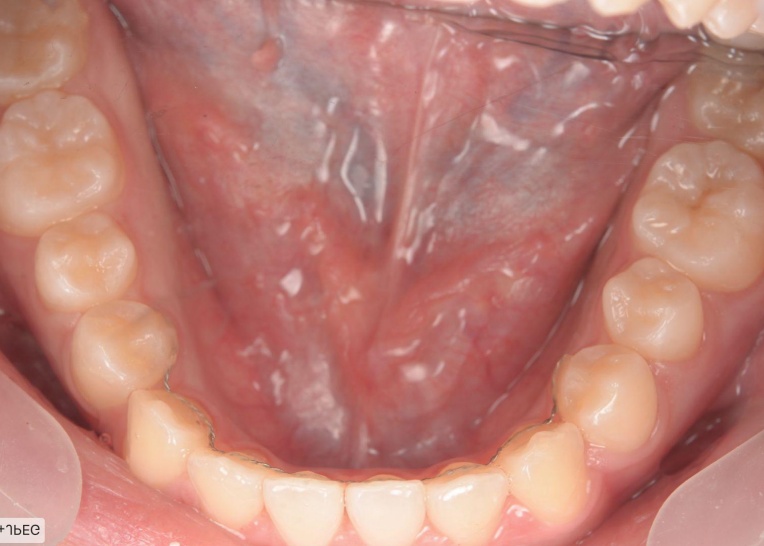

「前歯が噛み合わないので治したい」とご相談いただきました。 |

拝見したところ、重度の開咬(かいこう)が認められました。 |

見た目と噛む機能の両方を改善するため、矯正治療を提案し、同意いただきました。 |

18ヶ月 |